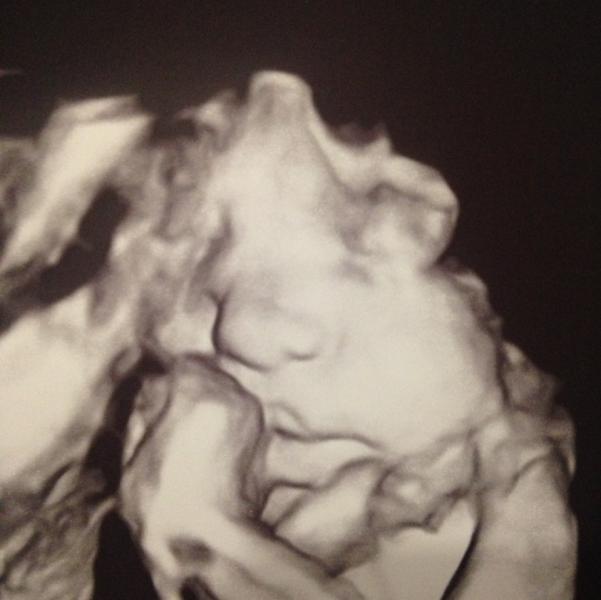

После бессонной ночи я все таки решила записаться на экспертное узи. Вот и доверяй после этого узи в жк! Хорошо что сходила на повторное как мне большинство посоветовали. Никакого маловодья и в помине нет, степень зрелости плаценты не 2 а 1, и главное, синдром задержки в развитии мне не подтвердили, ребенок маленький конечно, всего 1735, но сказали что это в пределах нормы для моего срока. Сосуда оказывается не 3 а 2 правда, но кровотоки в норме и еще однократное обвитие не тугое рассмотрели. В целом все хорошо, отклонений нет, никакого лечения не требуется. Центру медицины плода я доверяю, дорого конечно, но это стоит своих денег, теперь я спокойна, там действительно работают профессионалы, всем советую) даже мордашку моей девочки показали☺️ сказали губки бантиком, на маму похожа😁